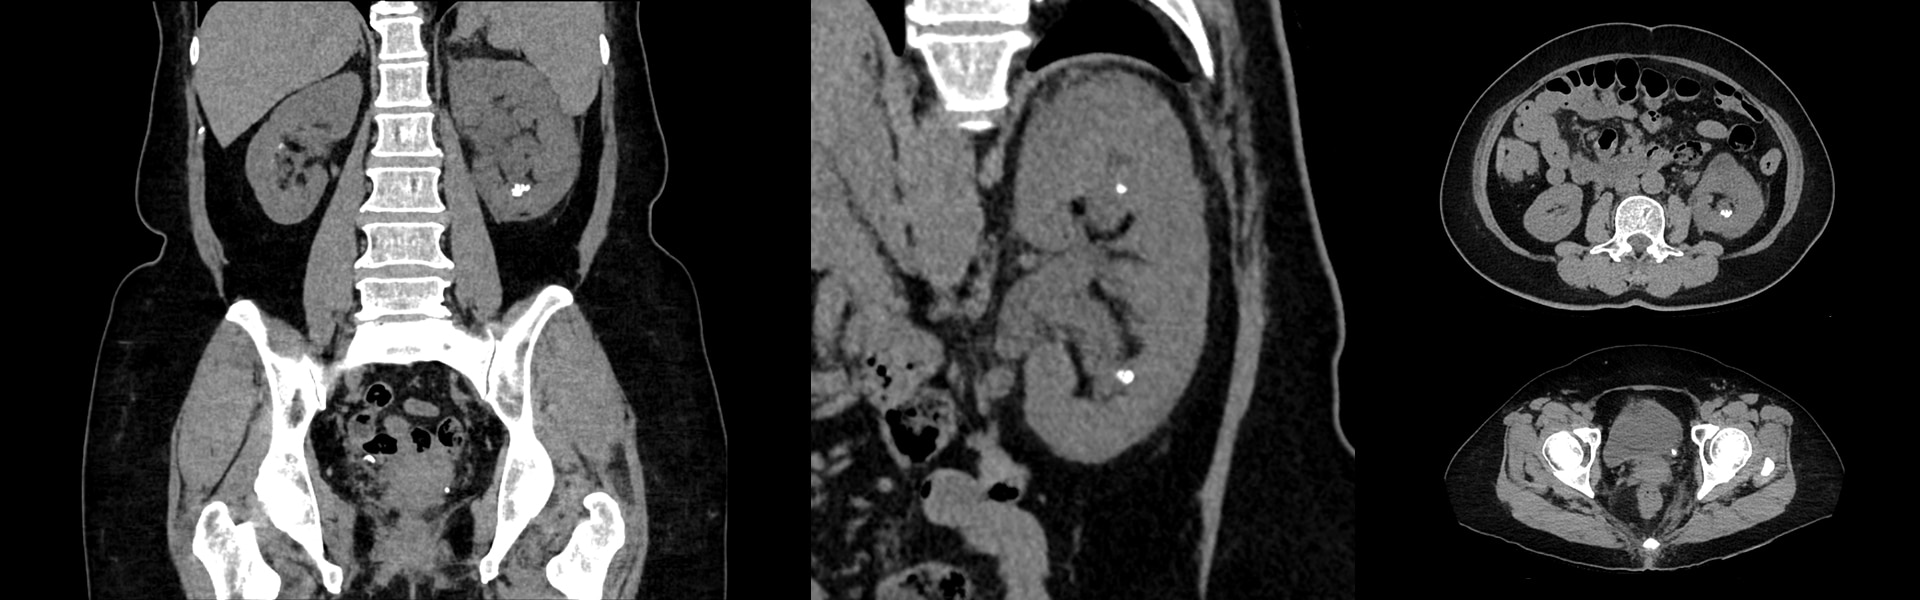

Images cliniques

Utilisation prévue : Le système Discovery MI Gen2 TEP/TDM est destiné à l’imagerie TEP corrigée de l’atténuation par TDM de la distribution des produits radiopharmaceutiques émetteurs de positrons anatomiquement localisée. Il est destiné à l’imagerie du corps entier, de la tête, du cœur, du cerveau, du poumon, du sein, de l’os, des systèmes gastro-intestinal et lymphatique, et d'autres Le système est également destiné à l'imagerie tomodensitométrique diagnostique (CT).